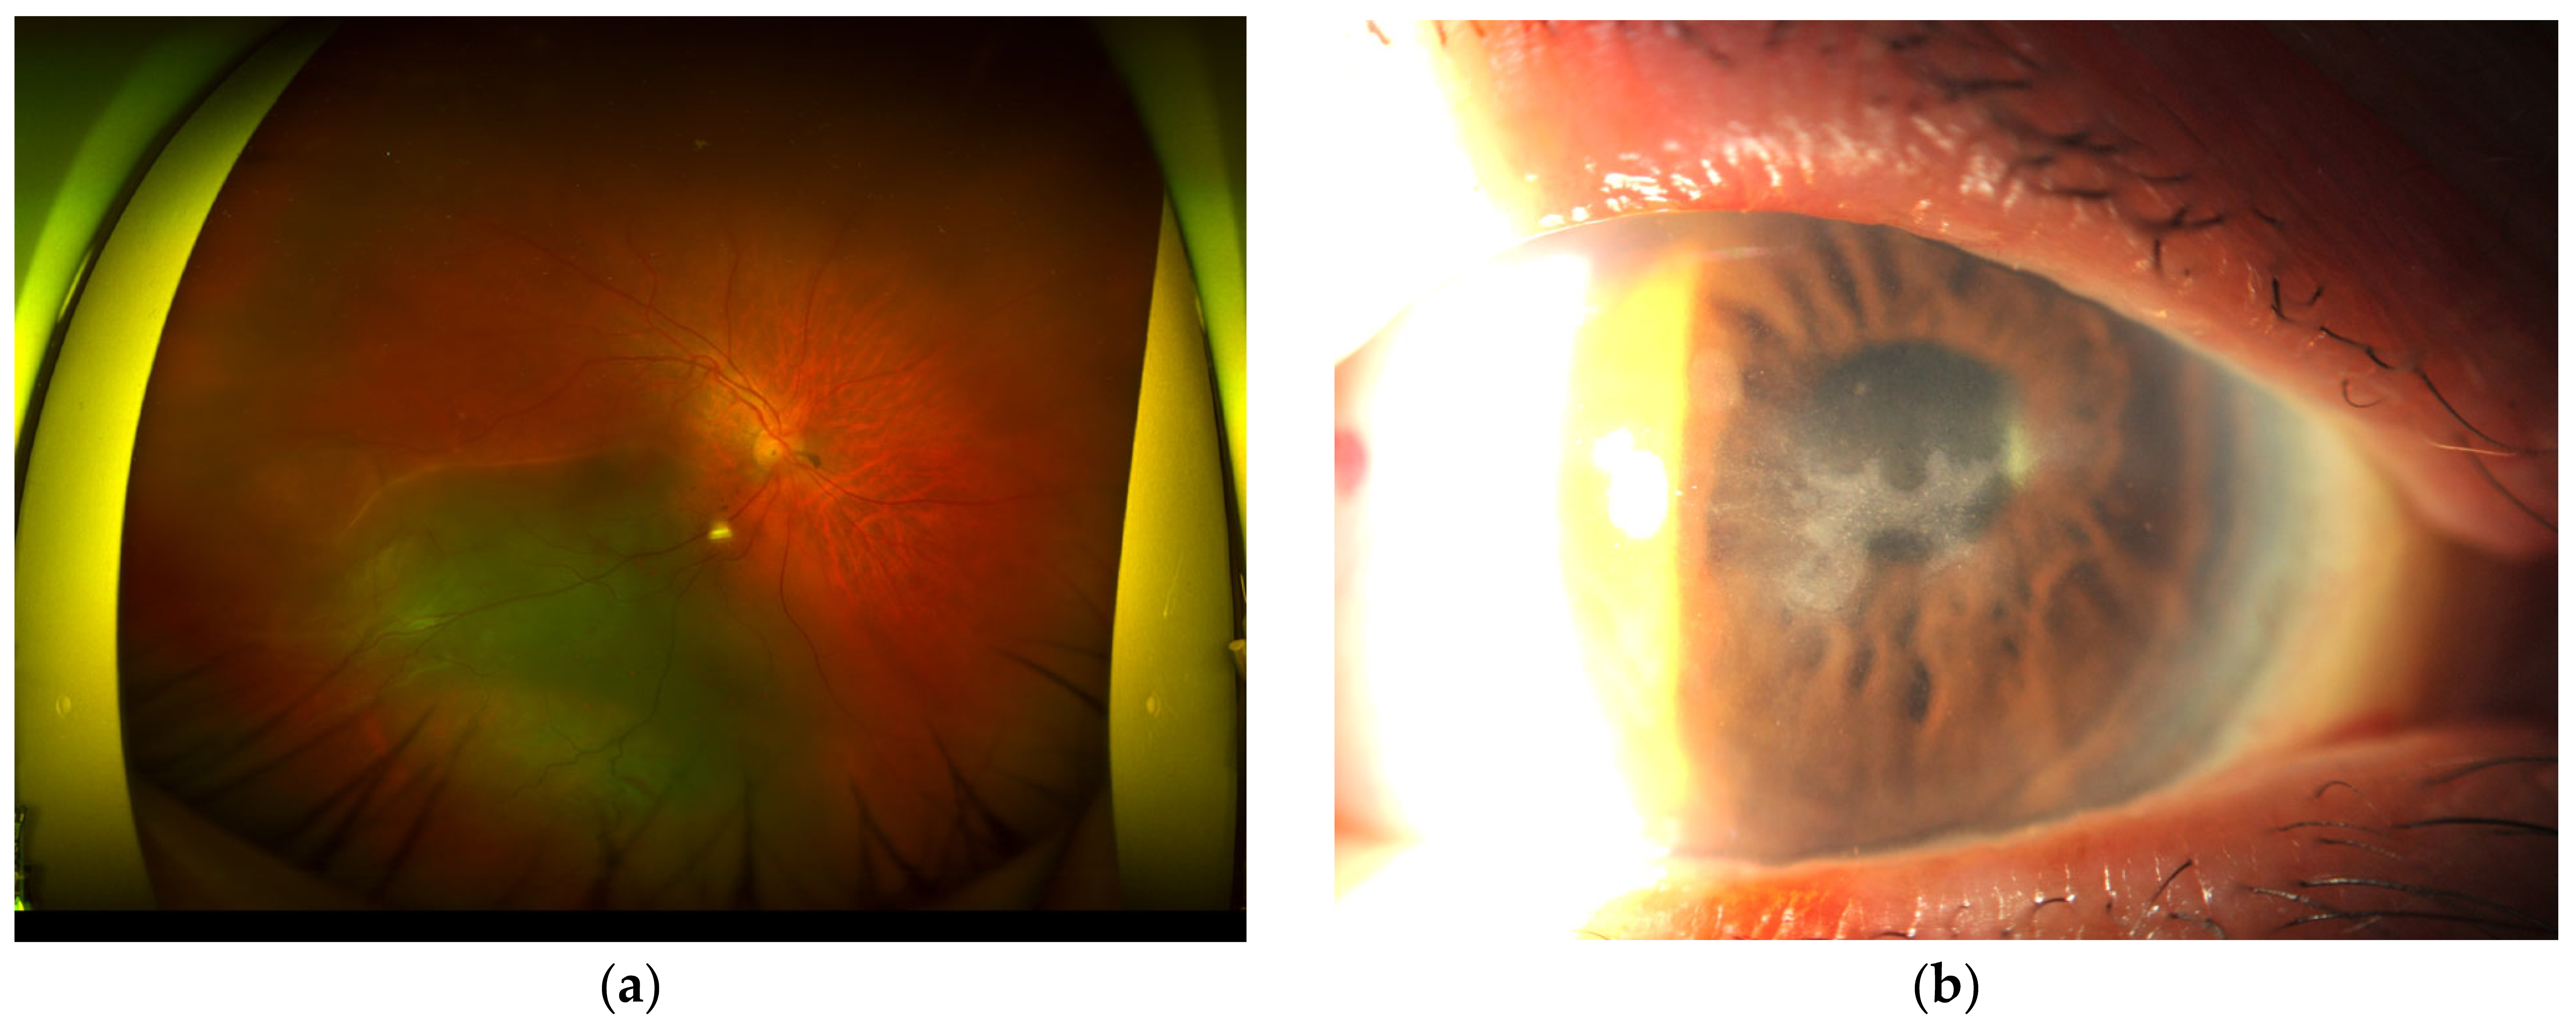

2. Case Presentation 1